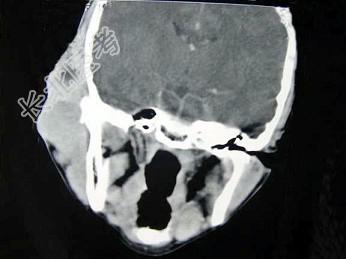

- 单项选择题女,19岁, 右侧面颊部肿胀1年,CT检查如图所示, 最可能的诊断是 ( )